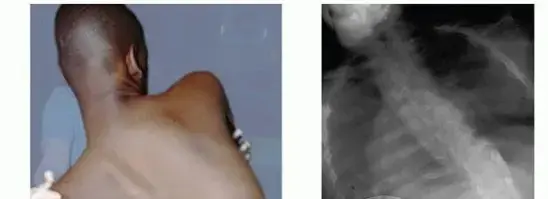

تشوهات العمود الفقري الجنف والحداب

تُعد تشوهات العمود الفقري، وبخاصة الجنف (Scoliosis) والحداب (Kyphosis)، من أكثر المشكلات العظمية شيوعًا وخطورة في مرضى NF1، حيث تصيب ما بين 10% إلى 25% منهم.

- الجنف التغذوي (Dystrophic Scoliosis): هذا النوع هو الأكثر تحديًا ويُعد مميزًا لـ NF1. يتميز بتقوس حاد ومتقدم بسرعة، وغالبًا ما يكون في المنطقة الصدرية القصوى أو الصدرية القطنية. يرتبط بوجود أورام ليفية عصبية داخل العمود الفقري أو حوله، والتي قد تؤدي إلى تآكل الفقرات أو ضعف في بنية العظام المحيطة، مما يجعل العظام هشة وعرضة للتشوه. يتميز هذا النوع بوجود تشوهات فقارية مثل خلل التنسج الفقري (vertebral dysplasia)، تآكل الضلوع (rib penciling)، واتساع الثقوب العصبية (neural foraminal enlargement). غالبًا ما يتطلب التدخل الجراحي.

- الحداب والجنف الحدابي (Kyphosis and Kyphoscoliosis): يُعد الحداب (انحناء الظهر للأمام) والجنف الحدابي (انحناء جانبي وأمامي معًا) أكثر شيوعًا وشدة في مرضى NF1 من الجنف وحده. غالبًا ما يكون الحداب في NF1 من النوع "الزاوِي" (Angular Kyphosis) ويكون متقدمًا، مما قد يؤدي إلى ضغط على النخاع الشوكي (Spinal Cord Compression) ويسبب ضعفًا عصبيًا أو شللًا. هذه الحالات تتطلب تقييمًا عاجلاً وتدخلًا جراحيًا عادةً.